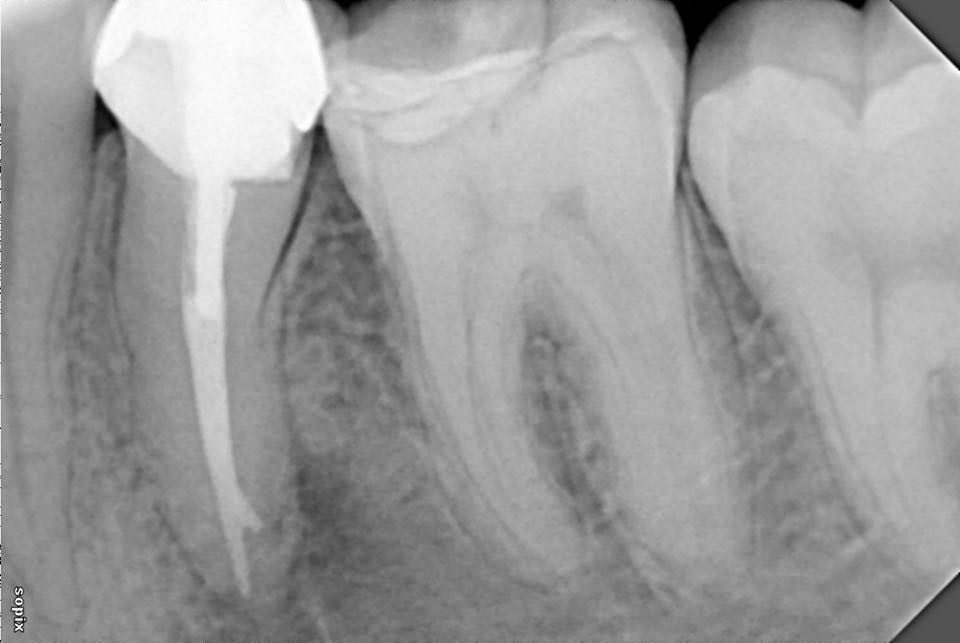

左下第二前磨牙根管再治疗

转自FB.根管再治疗,5个月随访,病变愈合良好。